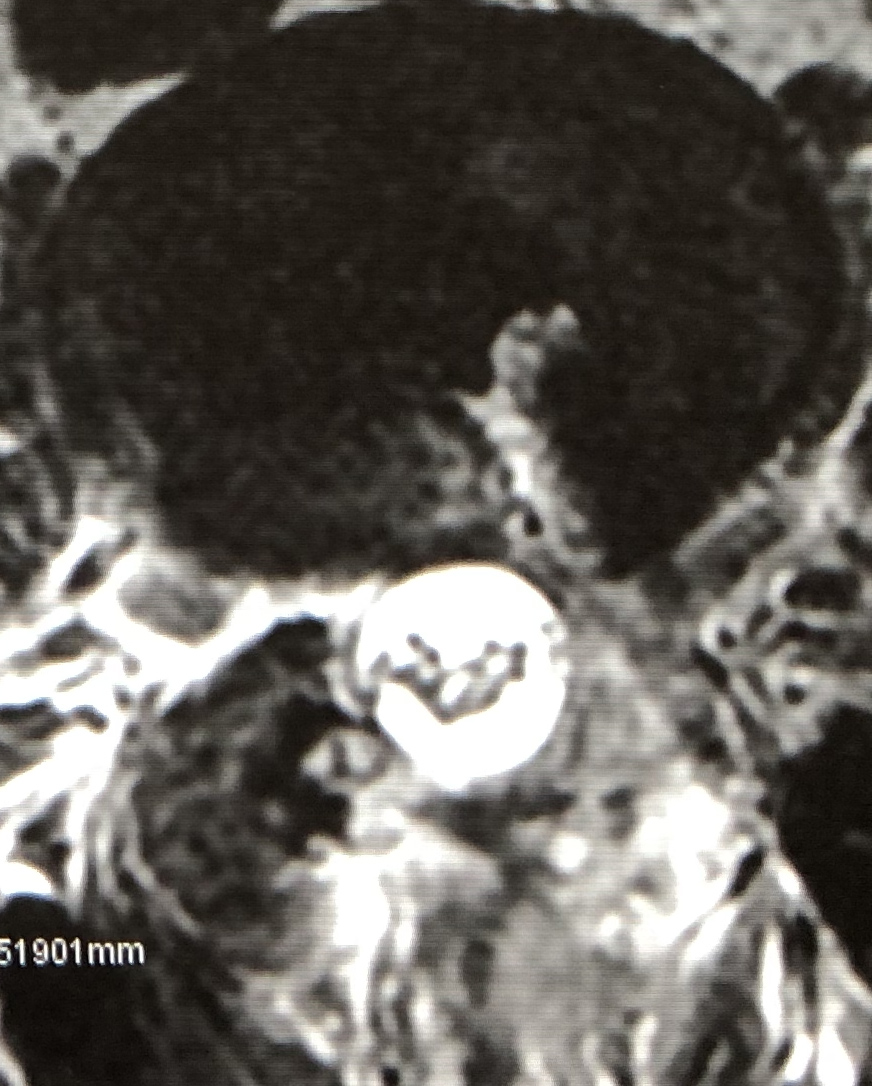

頚部脊柱管を後方から拡大し、脊髄の圧迫を除く手術方法です。

手術後は脊柱管が明らかに拡大しています。

| 術前 | 術後 |